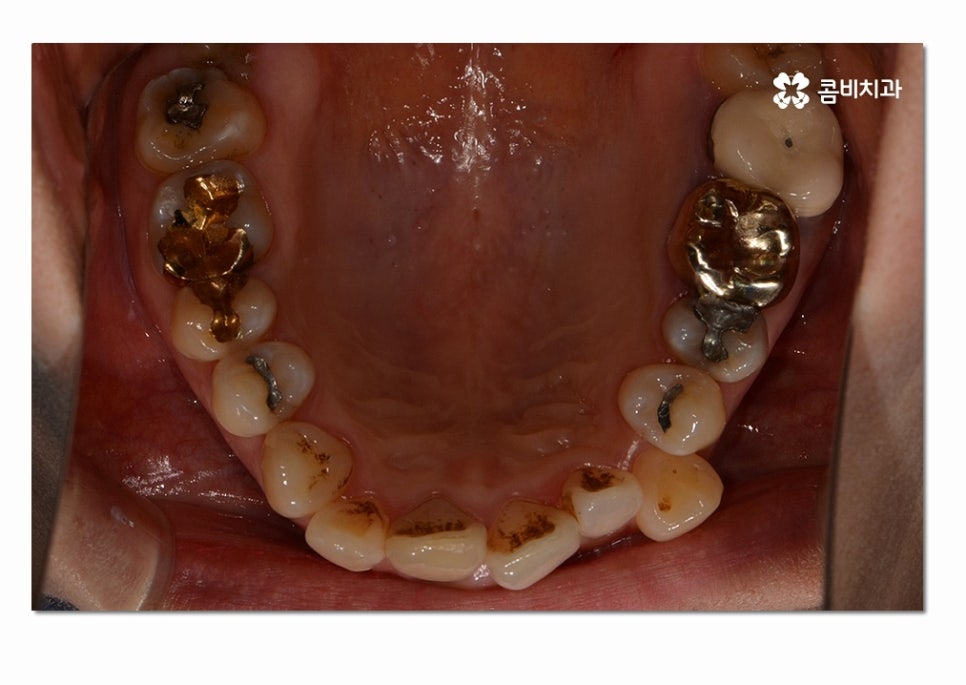

위 사례의 경우에는 3급 부정교합의 케이스로

치열이 맞지 않아 치아의 본래 기능들이 제대로 이루어지지 않고 있는 상태이며

서로 닿지 않아서 식사를 할 때마다 제대로 씹지 못하여

불편함을 느끼는 것은 물론이며 구강관리도 잘되지 않아서

충치가 많이 발생하고 있는 사례였다고 볼 수 있어요.

이러한 3급 부정교합은 나이가 들수록 구강 내 충치 및 잇몸질환의

발생률을 높일 뿐 아니라 음식물을 제대로 씹지 않아서

만성적인 소화불량을 겪기 쉽고 발음상의 불리함이나